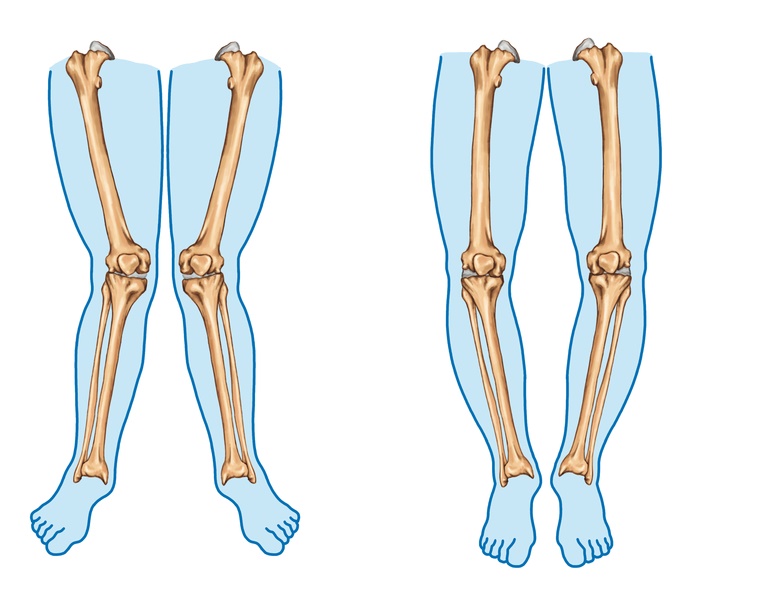

In most scenarios, its an over-concerned aunt or a nosy neighbour, who sets the alarm bells ringing in the parents minds. When they point out your child’s legs when in a gathering or a playground. Most Angular deformities around the knee, such as genu varum (bow legs) and genu valgum (knock knees), are common in children. These conditions refer to the inward or outward angling of the knees, which can be part of normal growth but sometimes require medical attention.

- Children with genu varum have knees that bow outward when the feet are together.

Genu Varum (Bow Legs):

Genu Valgum (Knock Knees):

- In genu valgum, the knees angle inward, causing the feet to be apart when standing with the knees together.